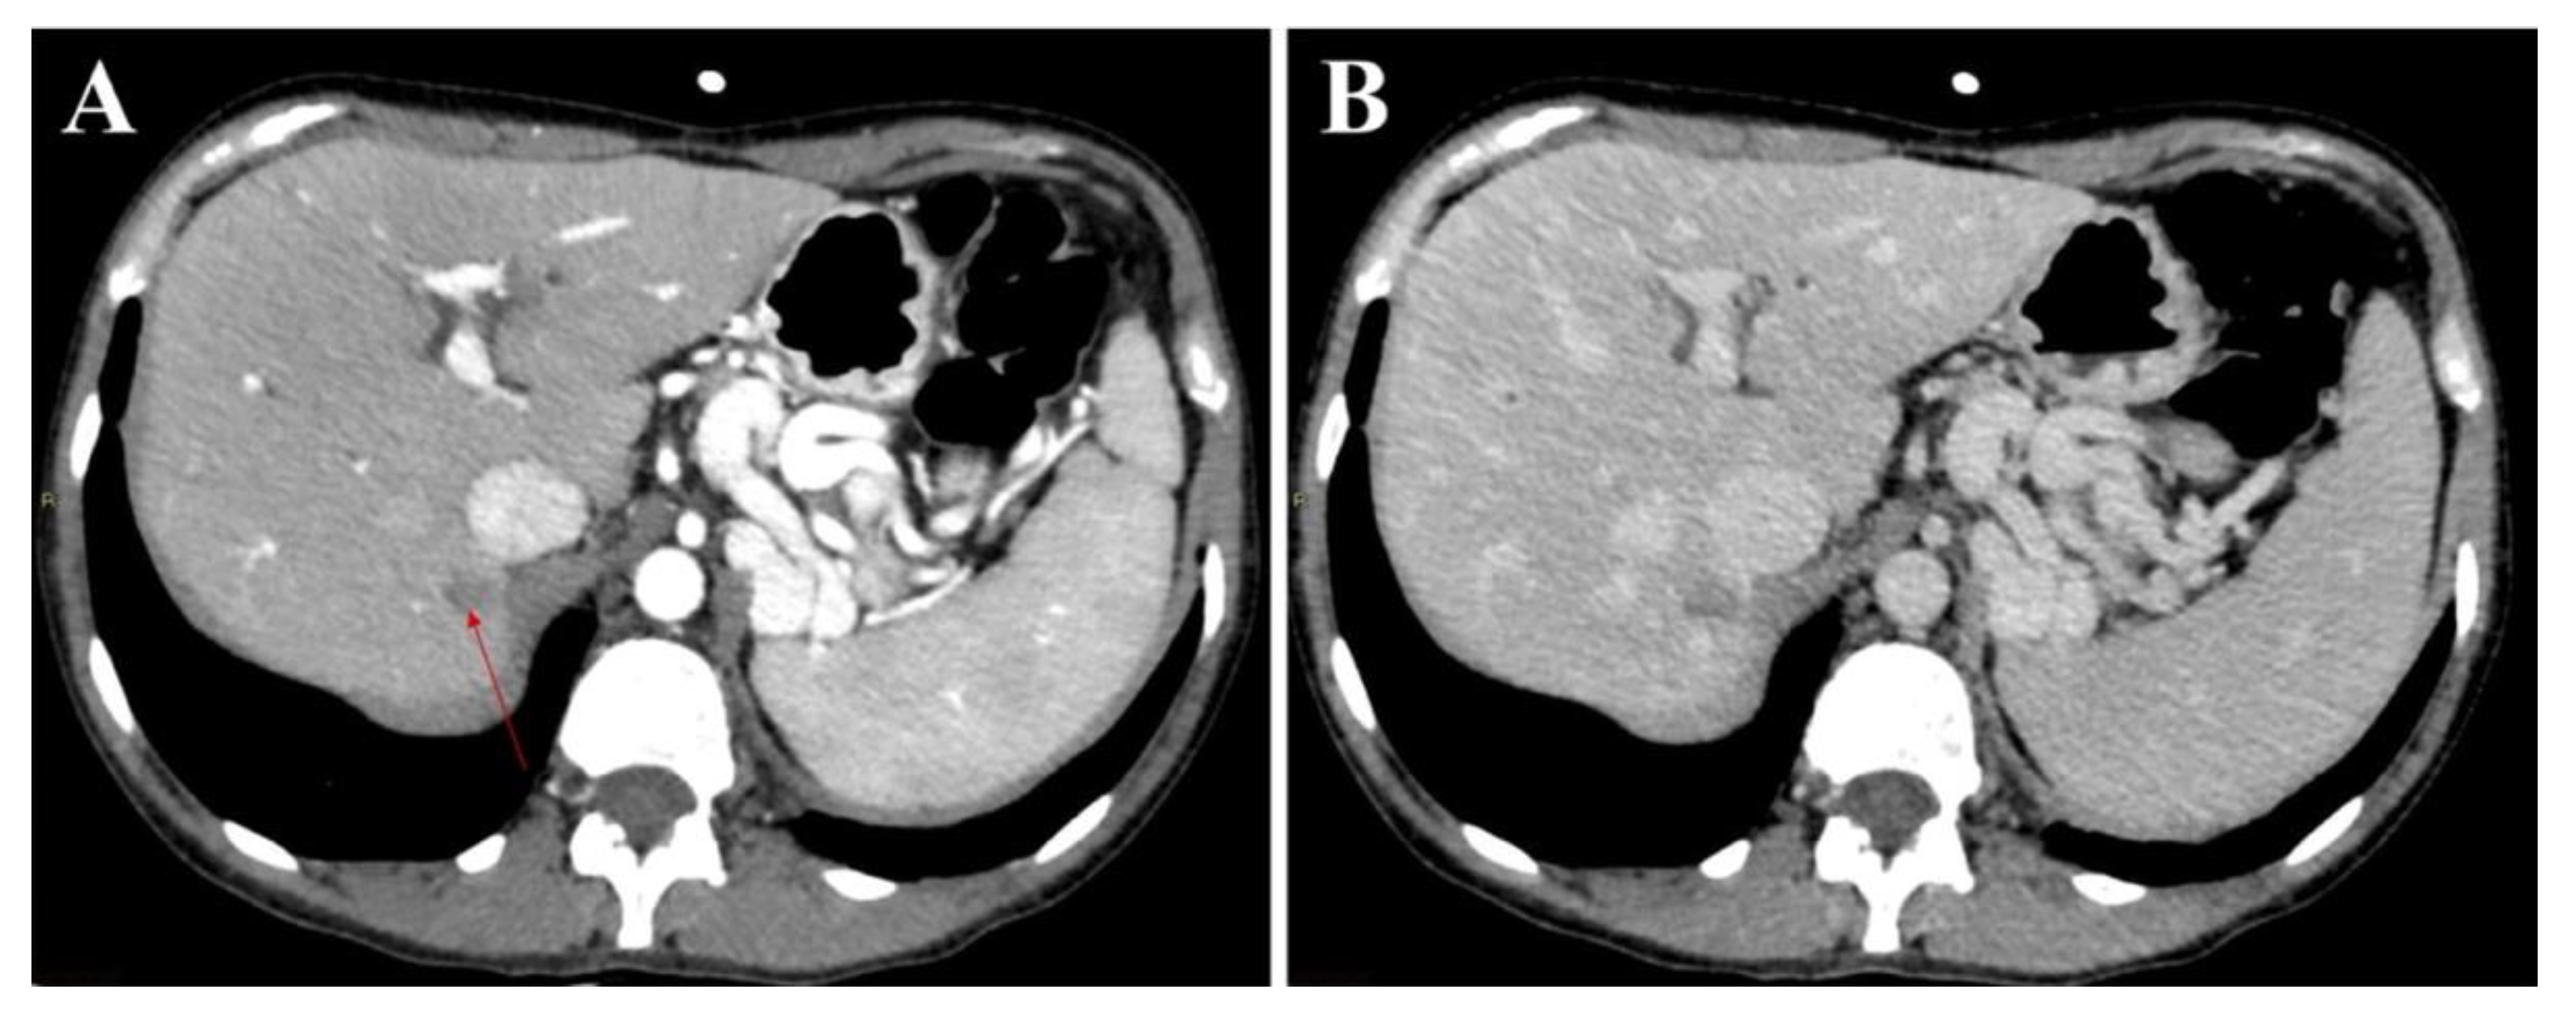

3.1. Atypical Liver Nodule Characteristics

3.2. Feasibility of Liver Biopsy

3.4. Factors Associated with the Unfeasibility of Biopsy